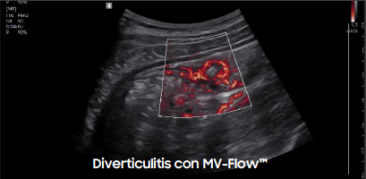

Calidad de Imagen Superior: Claridad, Profundidad y Precisión

El Samsung R20 ofrece tecnologías que garantizan imágenes nítidas, uniformes y de alto contraste en todo momento:

Gracias a estas tecnologías, el R20 garantiza diagnósticos visuales precisos incluso en estructuras complejas o difíciles de visualizar.

Galería de imágenes